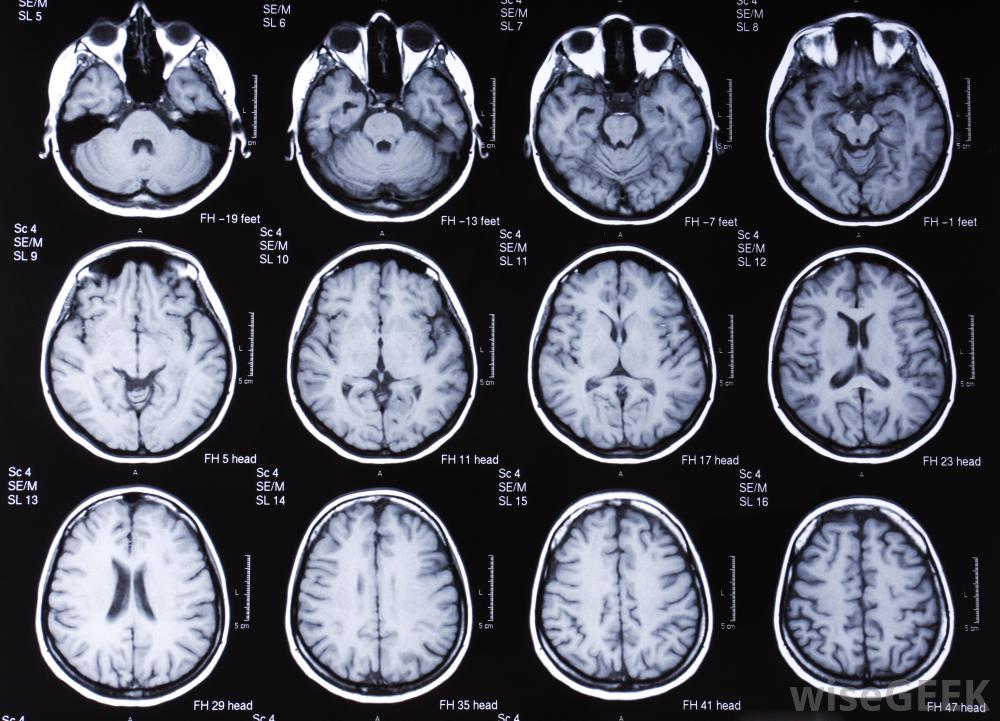

脑部的MRI扫描。MRI技术人员必须熟练操作MRI设备,并能够以某种方式治疗患者,专业态度。有意成为核磁共振技师的人必须在学校接受专业培训。学生可以选择获得副学士学位或学士学位

MRI技术人员可以在相邻观察室的屏幕上查看实时数字图像。MRI扫描仪是一个形状像甜甜圈的磁铁,在设备中间有一个隧道病人被安排在一张桌子上,桌子移动到隧道里。当病人在隧道内休息时,无线电波是用来拍摄人体内部的图像,所产生的图像可以转换成三维图像,以便更准确地诊断一种医疗状况。利用MRI可以诊断各种健康状况